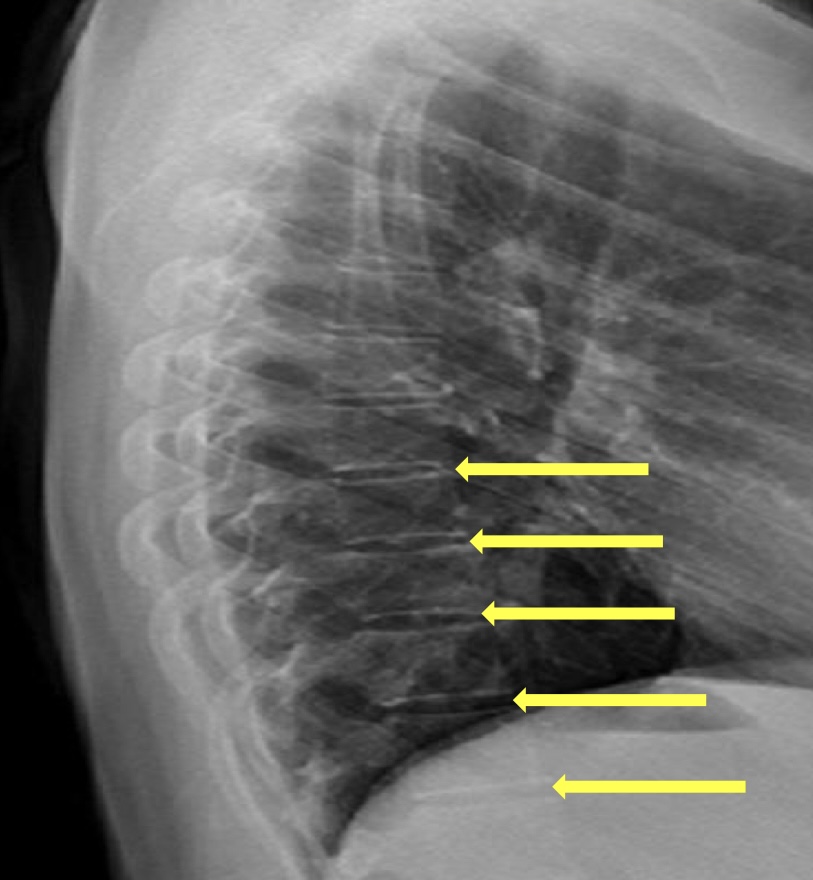

What view is this?

Lateral Thoracic

What is this?

Disc Spaces

What is this?

Endplate Tips